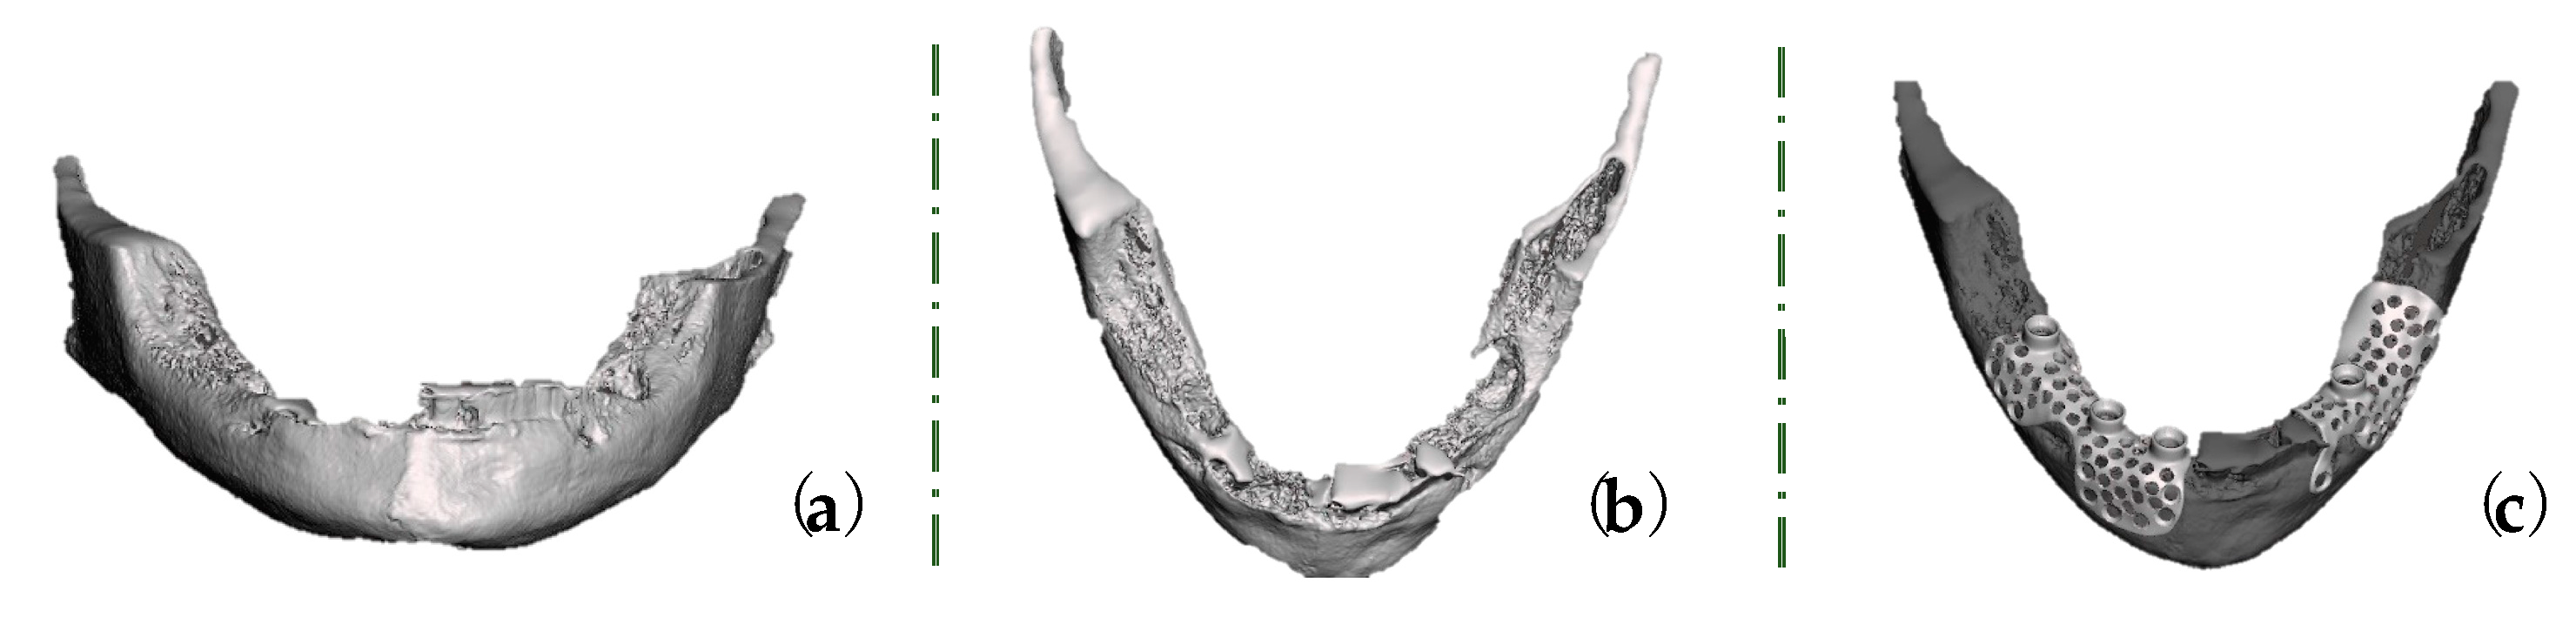

The data collected via CBCT and intraoral scans (Medit i700, MEDIT corp. 8, Seoul, Republic of Korea) were exported into Exoplan (exocad GmbH, Darmstadt, Germany), from which a standard tessellation (.STL) file was obtained.

The STL file was exported into DentalCAD 3.0 Galway software (exocad GmbH, Darmstadt, Germany) to reconstruct the bone loss and to design two customized meshes for each mandible side (Figure 4a–c).

Figure 4.

Virtual images of bone loss in (a) panoramic view and (b) axial view. (c) The designed custom-made titanium meshes.

The custom-made titanium meshes were designed with a 0.6 mm thickness, holes with a 2 mm diameter on the entire smoothened surface, rounded edges, and prosthetic connections (three for the right mandible side and one for the left side) and were compatible with Nobel Biocare multi-unit abutments (Nobel Biocare Services AG, Zürich-Flughafen, Switzerland).